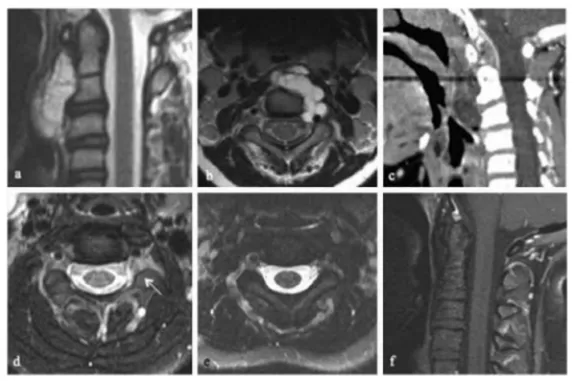

术后病理明确诊断为经典型脊索瘤,与术前预判一致。然而术后MRI显示,左侧C2至C3神经孔内仍有少量残余肿瘤。这是脊索瘤手术中较为常见的情形——由于肿瘤已侵入神经孔,为最大程度保护神经功能,不得不保留极少量组织。对于这部分残余肿瘤,Rutka教授团队制定了70 Gy光子放疗方案。高剂量放疗能够有效控制残余肿瘤的活性,延缓乃至阻止复发。小明对整个治疗过程的耐受性良好,未出现严重的放疗相关并发症。

影像资料显示:(a)术前矢状位T1加权钆增强MRI;(b)术前轴位T1加权增强MRI;(c)术前矢状位CT;(d)术后轴位T1加权增强MRI,可见C2至C3神经孔内少量残余肿瘤(箭头所示);(e)放疗后轴位T1加权增强MRI;(f)放疗后矢状位T1加权增强MRI。